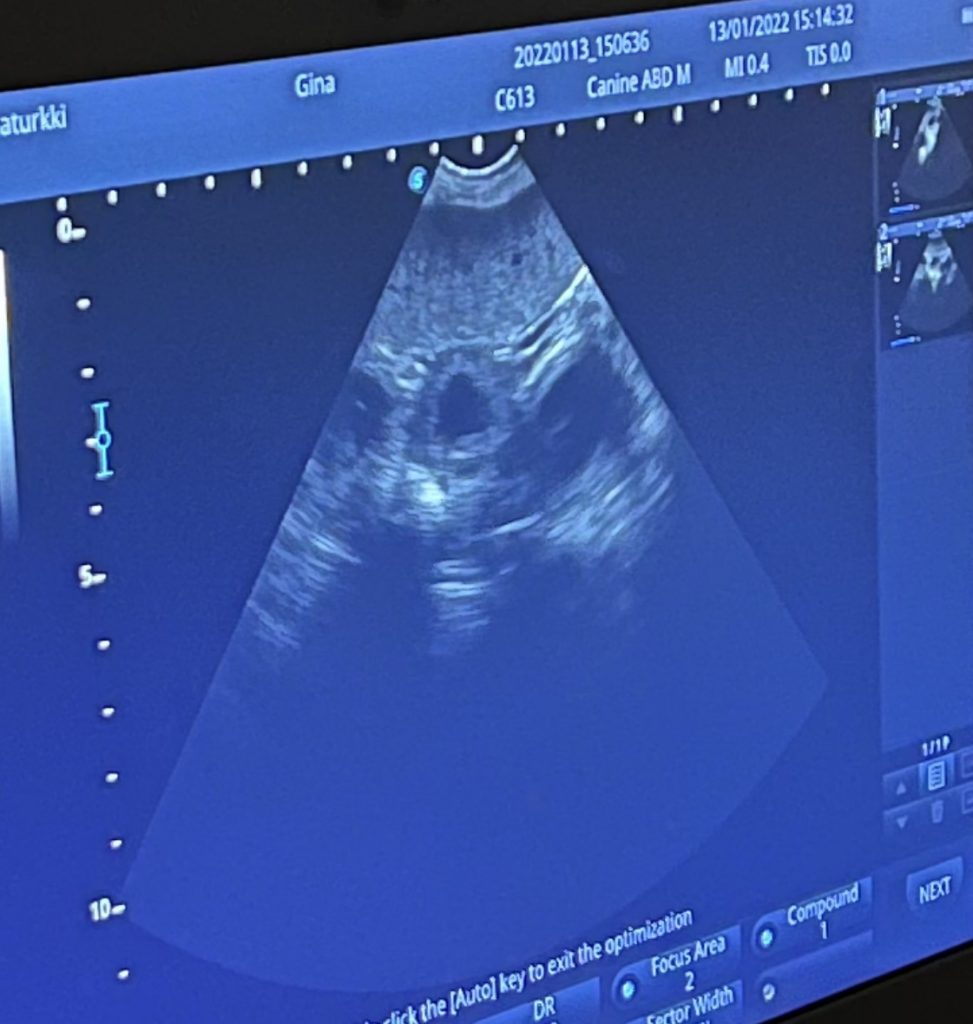

Pentuhaaveet vahvistuivat, kun Gina kävi tänään ultrassa. Jos kaikki sujuu hyvin, saamme pentusia Ystävänpäivän aikoihin ❤️

Muutama pieni bullan alku bongattu tänään tiineysultrassa 💕 Nyt toivotaan, että kaikki sujuu hyvin ja pääsemme nuuhkuttelemaan pennun tuoksua pentulaatikon laidalle syyskuun alussa 🥰